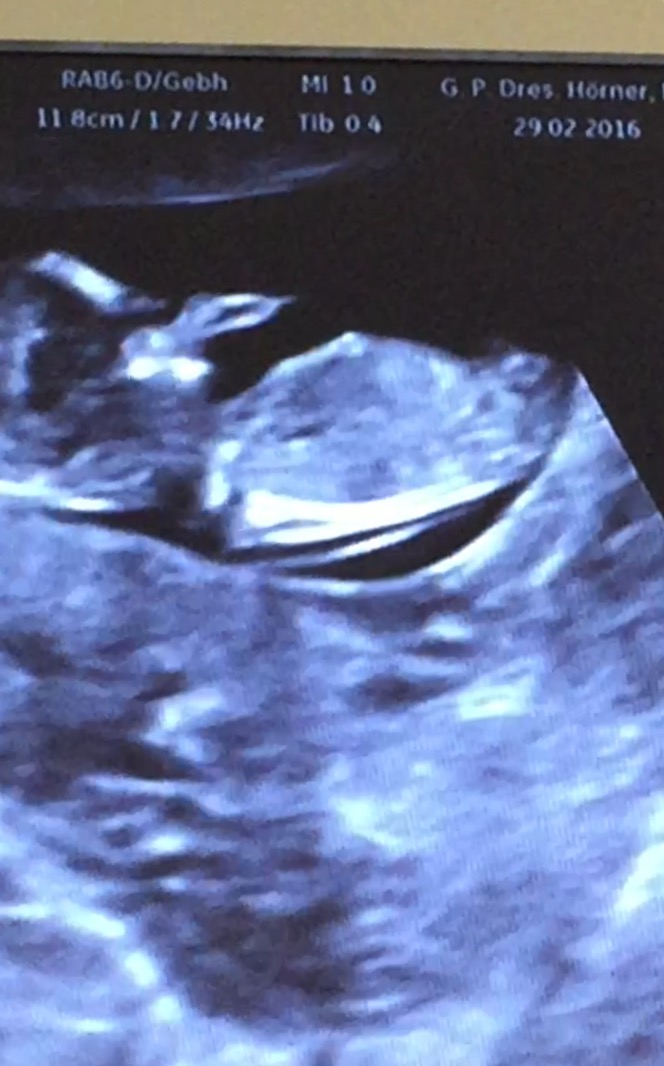

my doctor is leaning Boy because of something sticking out looking at the potty Shot, but said it was early... He did not know the Nub Theory, so I'm asking you Girls, is this a reliable picture? I have a video and am trying to cut some good Positions, but Baby is turning round all the Time...

Attachment 30177